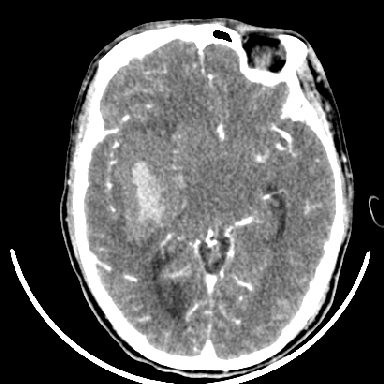

标题: CT6056:脑出血(血管畸形?)

m 40突发头痛左侧偏瘫3小时

考虑高血压性脑出血,依据:

1是高血压性脑出血的好发部位,形态呈肾形,是高血压性脑出血的常见形状

2增强时占位效应加重了,考虑出血还没有停止

3病灶周围水肿不是太厉害,一般肿瘤出血水肿多非常明显

4病灶周围的‘软组织’影没有明显的强化

5至于脑血管畸形引起的出血,暂时没有看到明显的畸形血管影,也不太支持

支持右侧基底节脑出血

右侧基底节区脑出血.

支持右侧基底节区(主要为外囊区)原发性脑出血。

但脑出血早期做增强是不是有点太冒险了?

另附部分资料:“血液溢出血管外形成血肿,其内含有大量血红蛋白、血浆白蛋白,球蛋白,因这些蛋白对x线的吸收系数高于脑质,故ct呈现高密度阴影,ct值达40~90h,最初高密度灶呈非均匀一致性,中心密度更高,新鲜出血灶边缘不清。基底节区血肿多为“肾”型,内侧凹陷,外侧膨隆,因外侧裂阻力较小,故向外凸,其它部位血肿多呈尖圆形或不规则形”

术中抽出40ml陈旧血液,血肿底部似见一条索血管影